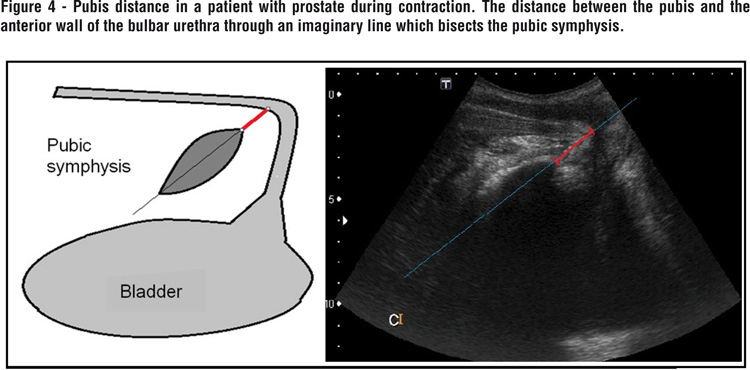

The pubis distance was defined as the distance between the pubis and the anterior wall of the bulbar urethra through an imaginary line which bisects the pubic symphysis (Figure 4).